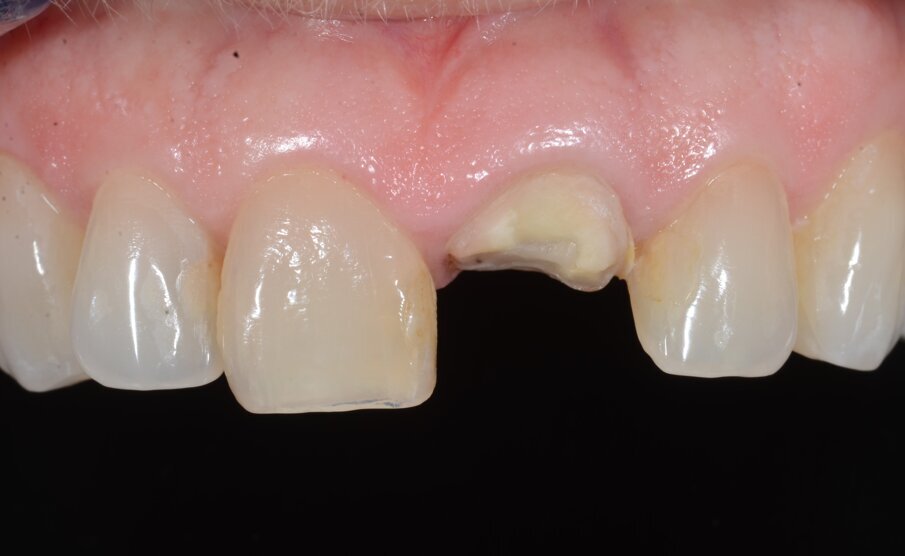

Una paziente di 53 anni si è presentata in studio con un incisivo sinistro fratturato a cui era stata più volte cementata una corona di ceramica (Figg. 1, 2). L’anamnesi e gli esami hanno evidenziato una buona salute sistemica e orale, un’occlusione ben equilibrata e nessuna abitudine al fumo. La tomografia cone beam (CBCT) e la radiografia periapicale hanno mostrato un riassorbimento radicolare esterno con inserimento nell’osso alveolare molto scarso, insufficiente per un adeguato posizionamento di un comune perno endocanalare (Figg. 3, 4). Considerando che il dente fratturato si trovava nella zona estetica, il paziente richiese un restauro nel modo più sicuro e più veloce possibile.

Fig. 2_Situazione iniziale, visione intra-orale.